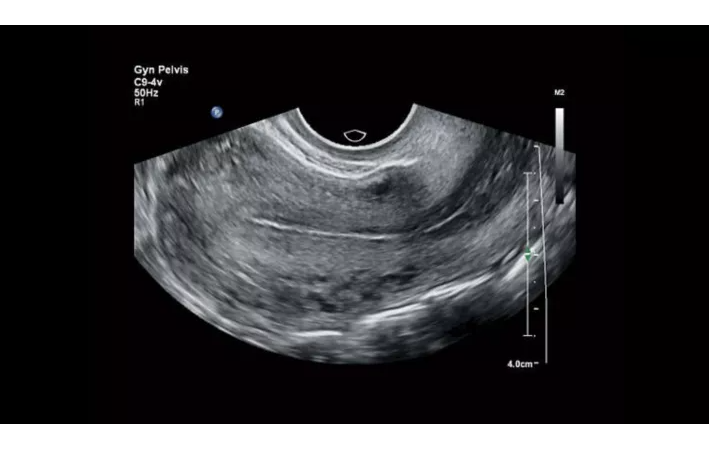

Функции для гинекологии и акушерства

- Free Hand 3D - возможность реконструкции 3D изображения при помощи линейного или конвексного датчика

- 4D Imaging - автоматическая визуализация 3D/4D изображения

- TrueVue - виртуальный источник света для получения качественного 3D/4D изображения

- FlexVue - опция для визуализации 3D изображений в плоскости

- aBiometry Assist - автоматические биометрические измерения